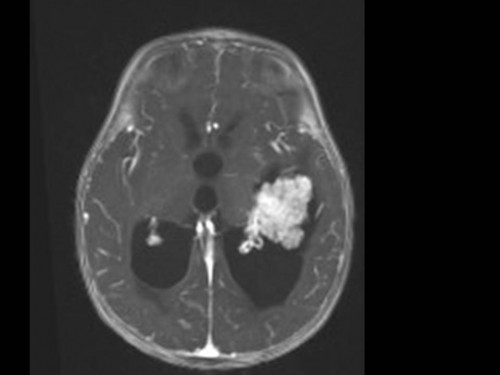

10 Monate altes Mädchen. Der Kinderarzt stellt fest, dass das kleine Mädchen einen recht großen Kopfumfang hat, nicht mit den Augen fixiert und anscheinend auch nicht richtig sehen kann. Damit bestätigt er die größten Befürchtungen der Eltern, denen in den letzten Wochen aufgefallen war, dass ihre Tochter nach keinem Spielzeug mehr greift und sie nur dann anlächelt, wenn sie zu ihr sprechen.

Bildgebung - MRT